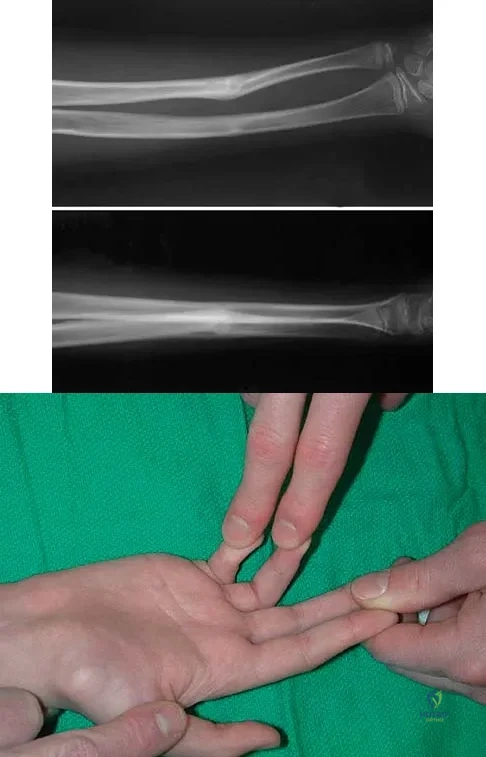

Question 60

A 12-year-old boy sustained a both bone forearm fracture 10 weeks ago and underwent closed reduction and casting. Examination now reveals that the injury is healed, but he is unable to extend his little and ring fingers of the injured hand with his wrist extended. Full extension is possible with the wrist flexed. A radiograph and clinical photograph are shown in Figures 15a and 15b. The remainder of his hand and wrist examination and neurologic evaluation in the hand are normal. What is the most likely diagnosis?

Explanation